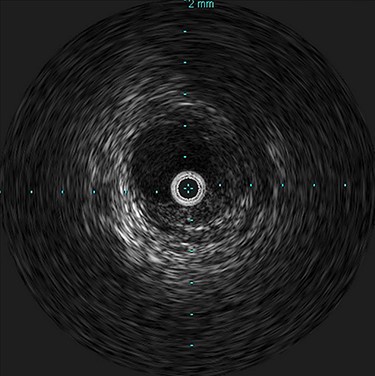

She was admitted and maintained on bowel rest and heparin infusion. Given persistent pain after 2 days of non-operative management, an abdominal arteriogram was performed through a left axillary artery cutdown. The dissection was identified 1.5 cm distal to the origin of the SMA (Fig. 2). Intravascular ultrasound was used to determine diameters and landing zones for stent placement (Fig. 3). The dissection was initially treated with a 6 mm × 40 mm self-expanding stent followed by post-dilation with 4 mm × 40 mm and 6 mm × 40 mm balloons. A 5 mm × 19 mm stent graft was deployed proximally with small overlap and ~3-mm extension into the aorta. Completion angiogram showed <10% residual stenosis (Fig. 4). As the right external iliac artery dissection was small and asymptomatic, no intervention was performed.

Intravascular ultrasound probe within the true lumen, with false lumen visualized to the bottom right of the probe.